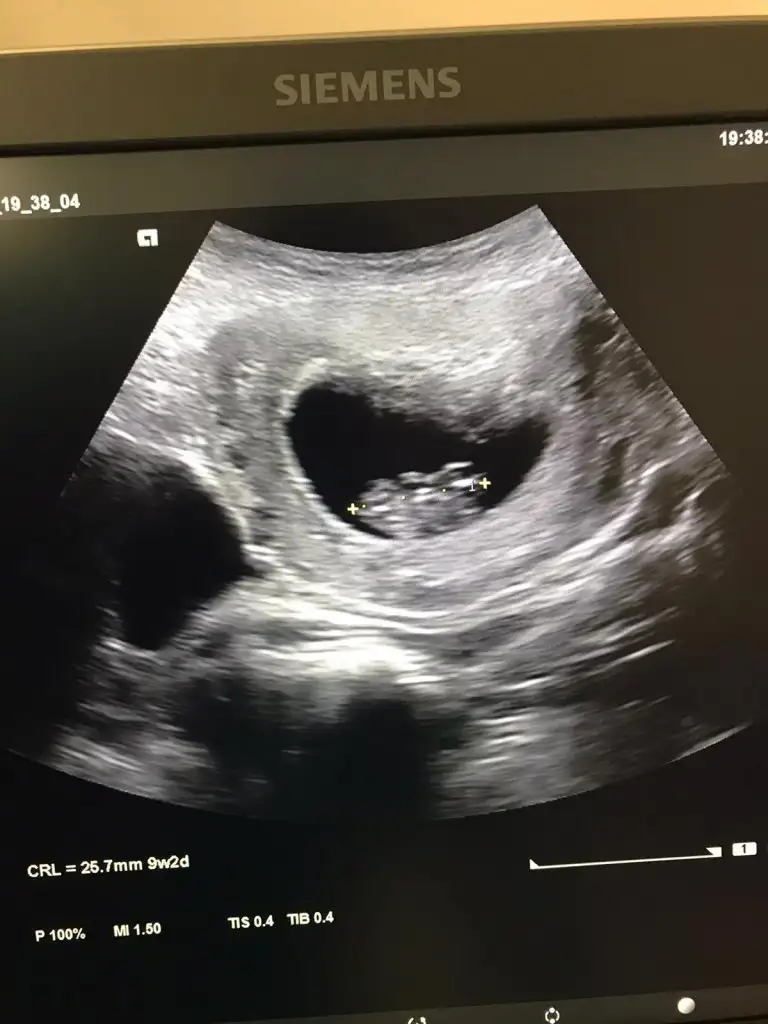

Erkek ve kız için 11 yada 12 hafta usg görüntüsü olmalı açıklamalar asagıda yazıyorrabbim herkesin gönlüne göre nasip etsin inşallah .. ecmain

[/B]Eki Görüntüle 473828 gordugunuz gibi ust taraftaki simgedende anlasildigi gibi eger cikinti paralel ise kiz

yok 30°lik bir aciyla yukari dogru bakiyorsa %99 oglunuz olacak demektir simdi bi kac ornek resimler daha koyacagim kiziminkide dahil

Eki Görüntüle 473829 bu bir erkek bebek genital nub cikintisi gayet yukarda

Eki Görüntüle 473831 simdi burada cikintilara bakin eger bel popo cizgisine paralel ise kiz

yok 30 derecelik bir aciyla yukari bakiyorsa erkek

yabancilarin hepsi biliyor bunu biz neden eksik kalalim gayet bilimsel simdi ellerinde11 12 13 ultrason fotografi olanlar alsin hemen baksin yada koyalim buraya yorumlayalim

KIz olabilirKizlar cinsiyet tahmininde bulunabilir misiniz :) dr bisey demedidaha